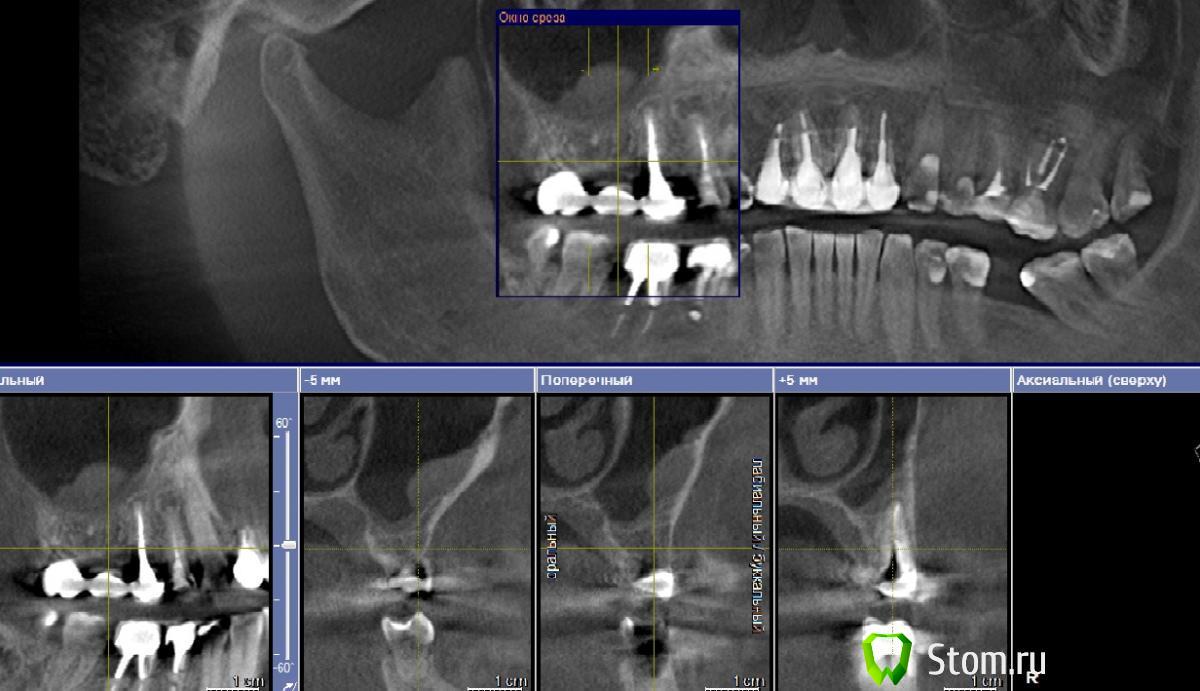

viruzzz Опубликовано 12 февраля, 2012 Поделиться Опубликовано 12 февраля, 2012 Нужен совет коллег!! как бы вы поступили в данной ситуации? что посоветуете?Знакомая обратилась с желанием иметь зубы.. Уже было сделано КТ (снимок прилагаю), где имеется утолщение слизистой пазухи в области давно удаленного 16 зуба. на данный момент 17 зуб уже удален и мост снят. на 15 и 14 имеются гранулемы. Больше склоняюсь к их удалению.До дна пазухи в области 16 зуба 4.5мм кости. Была у 2 ЛОРов: один говорит можно делать синус (МЕДИ), другой говорит не стоит (ЛОР НИИ). у меня дилема...удалить 14, 15, затем через 3-4 мес сделать контрольную КТ и думать снова? но если ничего не изменилось?не обращать внимания на утолщение в пазухе?с чем можно столкнуться в процессе и чем рискую?Спасибо за любые советы и комментарии Ссылка на комментарий

Elenushka Опубликовано 12 февраля, 2012 Поделиться Опубликовано 12 февраля, 2012 13 тож гранулема, а есть прицельный в обл 16,17, кое-что не нравится, и орту бы. наверное сначала бы сделала санацию синуса и удаление зубов. покажите снимок в обл 16,17извиняюсь,но не понимаю,что там оставшиеся корни или только материал, который бы убрать. ну и синус потом. Ссылка на комментарий

viruzzz Опубликовано 12 февраля, 2012 Автор Поделиться Опубликовано 12 февраля, 2012 еще раз просмотрел КТ.. остатков корней нет. есть киста от 17 и карман у 15 зуба с дистальной пов-ти.пазуху на санацию? отправить к ЛОРам, чтобы вырезали все? но один говорит, что все хорошо, а другой - если не беспокоит, то не трогать Ссылка на комментарий

viruzzz Опубликовано 12 февраля, 2012 Автор Поделиться Опубликовано 12 февраля, 2012 Я бы не переживал из-за этого, а спокоино бы ставил. Я в Лорнии работаю(как ЧЛХ), так наши лоры не все одинаково продвинуты. В МЕДИ доктор подрабатывает тоже наш (ЛОРНИИ)- нормальный эндоскопист.Мир тесен в Меди не Науменко случайно? или путаю.. Спасибо, прибавили уверенности.такой еще вопрос: на КТ утолщение находится как бы на передней стенке пазухи и больше в области давно удаленного 16 зуба..еще у одной пациентки на КТ видел утолщение слизистой тоже на передней стенке значительно выше корней зубов.. что это? как вообще правильнее назвать то, что в пазухе? киста? полип? просто утолщение? Ссылка на комментарий

kmatv Опубликовано 12 февраля, 2012 Поделиться Опубликовано 12 февраля, 2012 не путаете...мы с ним давно нормально и продуктивно работаем. Утолщение м.б. как рубцовое изм после ранее перенесенных синуситов. Утолщения то разные бывают. Именно в данной ситуации это действительно остаточные изменения, не полипы, не киста. Я ставил кучу раз и открыто и закрыто- все т.т.т. было нормально. 1 Ссылка на комментарий